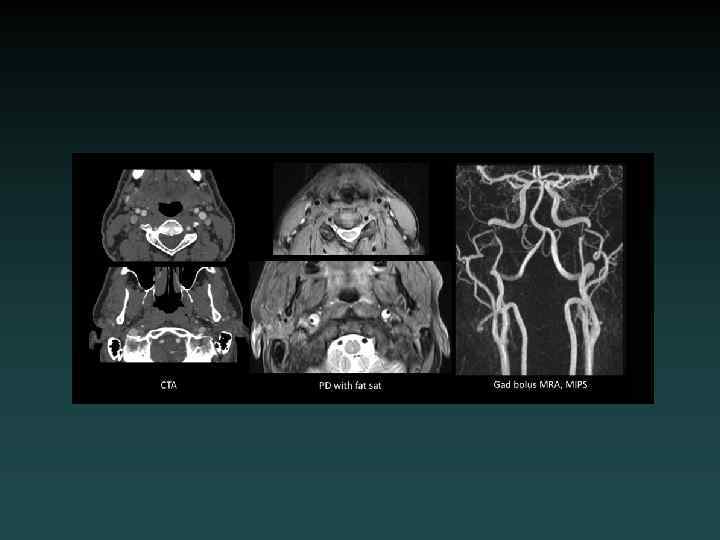

Which study? Vascular • CTA: – Neck: Aortic arch through Circle of Willis. – Head: Circle of Willis only • MRA: – Brain: noncontrast – Neck: without and with contrast.

Dural Sinus Thrombosis • Occlusive thrombosis • Subtle early signs – Bilateral infarcts – Hemorrhages • CTV or DSA – Filling defect • MRI/MRV

Aneurysmal SAH • Sudden severe headache • HYPERDENSE CSF spaces • Location – Interhemispheric: ACo. A – Sylvian: MCA • HYDROCEPHALUS, VASOSPASM and ISCHEMIA – MUST find the aneurysm! • DSA, CTA and/or MRA